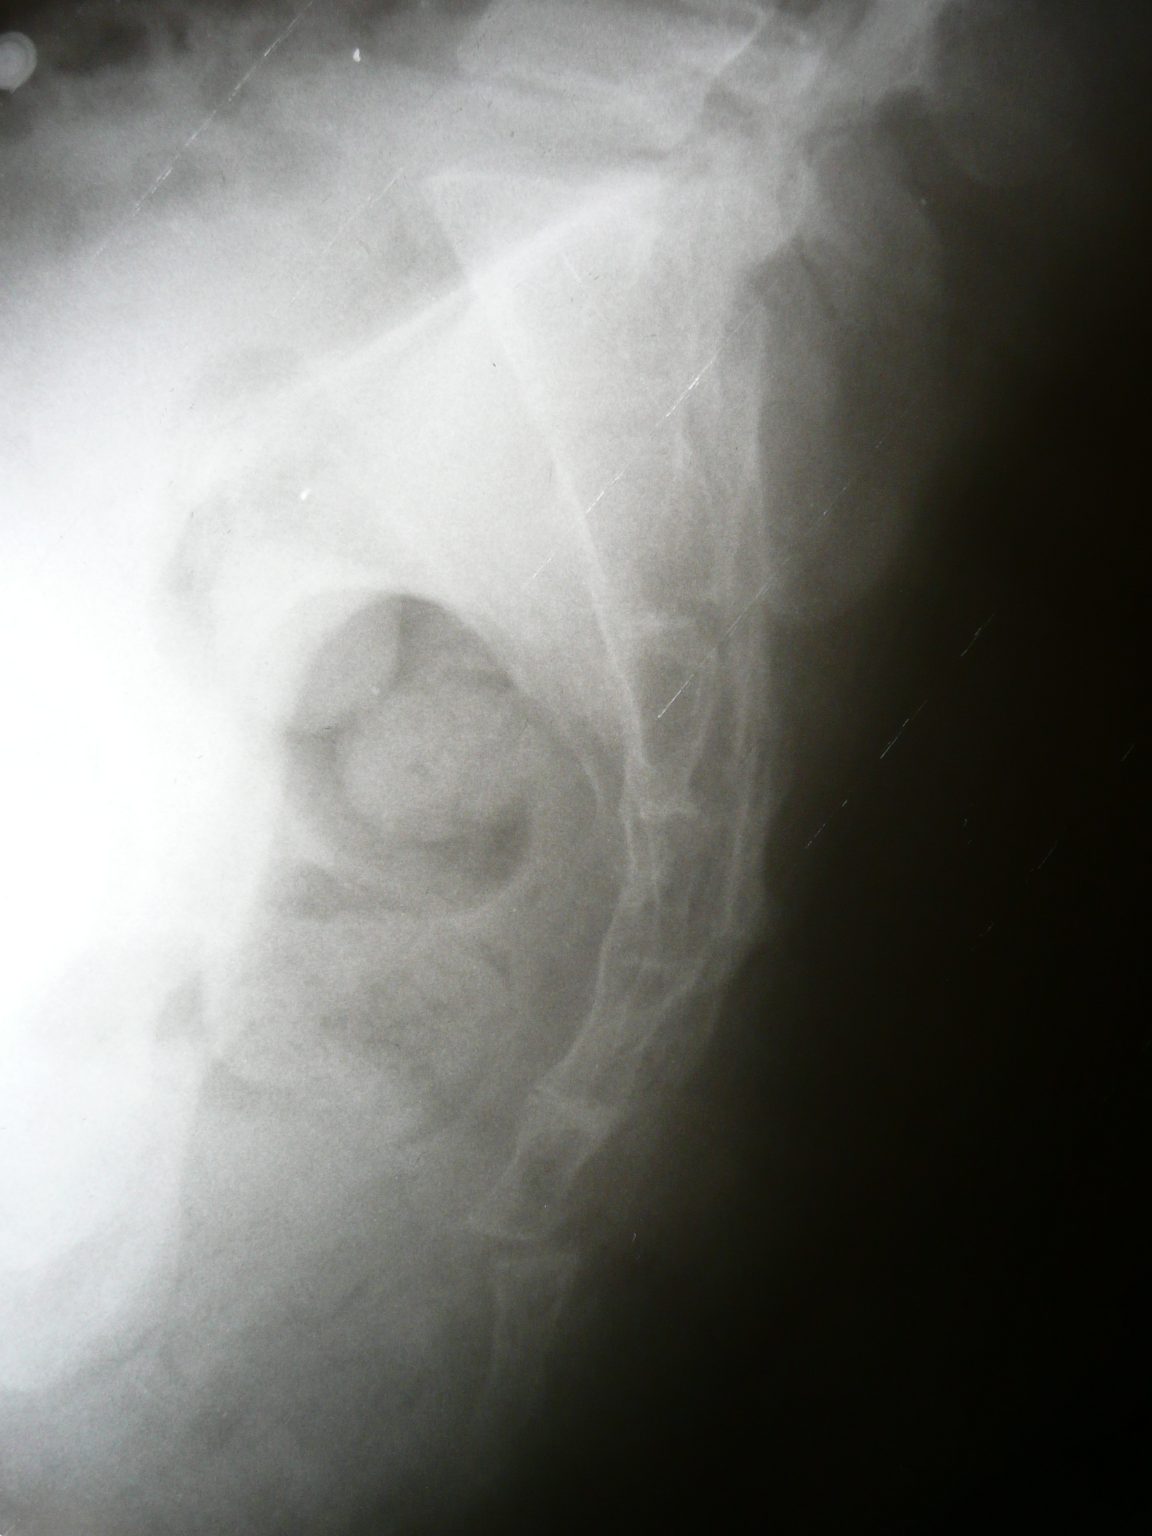

coccyx fracture lateral sacrum ray tailbone bone radiopaedia fractured treatment anatomy radiology figure sacrococcygeal case

Webuma fratura no cóccix ocorre quando há quebra ou trinca nas vértebras coccígeas, as quais compõem o osso cóccix localizado na parte inferior da. Webexames de imagem como rx pode ser solicitado pelo especialista para identificar o posicionamento que o cóccix se encontrar e avaliar se houve fratura. Webos sintomas incluem dor em um ou ambos os lados da região lombar e dor aguda (ciática) em uma ou ambas as pernas. O diagnóstico é feito através de. Webo diagnóstico é realizado pelo quadro clínico e exames de imagem. O quadro clínico é basicamente a dor localizada pontualmente sobre o cóccix, na maioria. Webcorrigir a maneira de se sentar é uma simples atitude que pode fazer a diferença e, sim, aliviar a dor no cóccix. A postura ideal para prevenir e aliviar esse. Quais são as principais causas das dores no cóccix? A região do cóccix, localizada na parte inferior.

A falta de ergonomia e quedas do dia a. Os exames de imagem para diagnóstico de coccigodínea incluem radiografias na posição sentada e em pé, pelas quais é possível. Weba dor no cóccix, também conhecida como coccidínia, pode ter diversas causas e apresentar sintomas variados. Conheça os tratamentos disponíveis. Webum osso da cauda quebrado é uma fratura do cóccix.